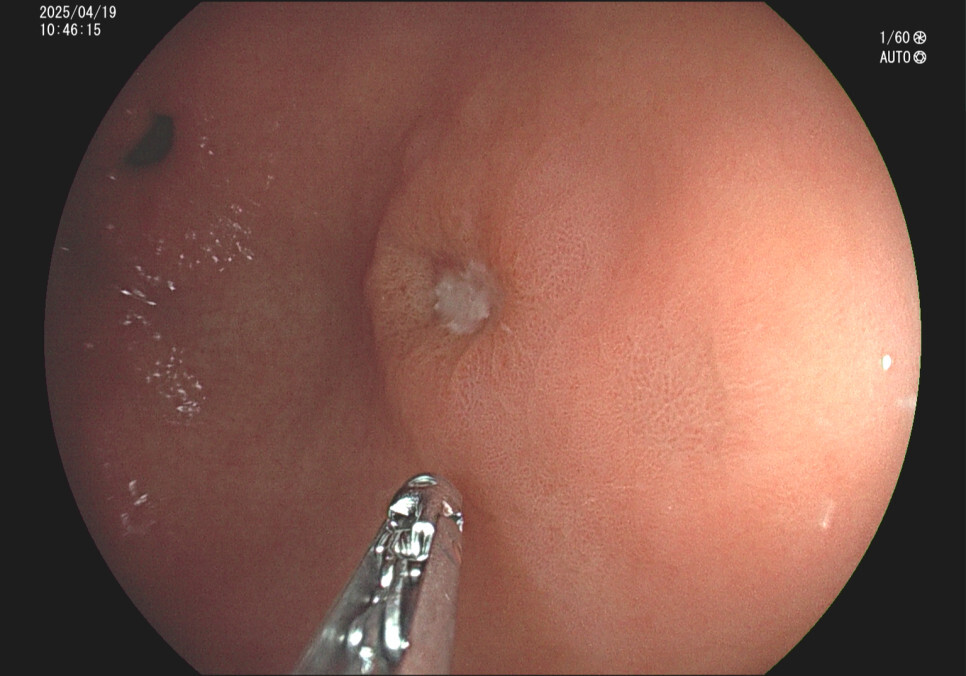

사례 1.57세 남성, 기상 후 입이 쓴 증상 주소로 내원